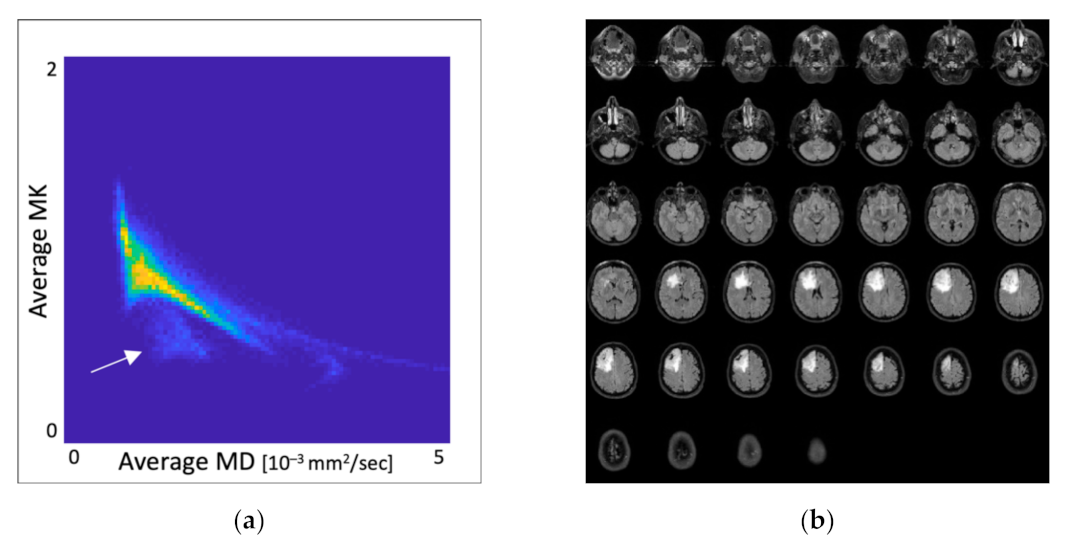

3.1. Distribution of MK and MD Values in Whole-Brain DKI Maps

3.2. Overlap Analysis